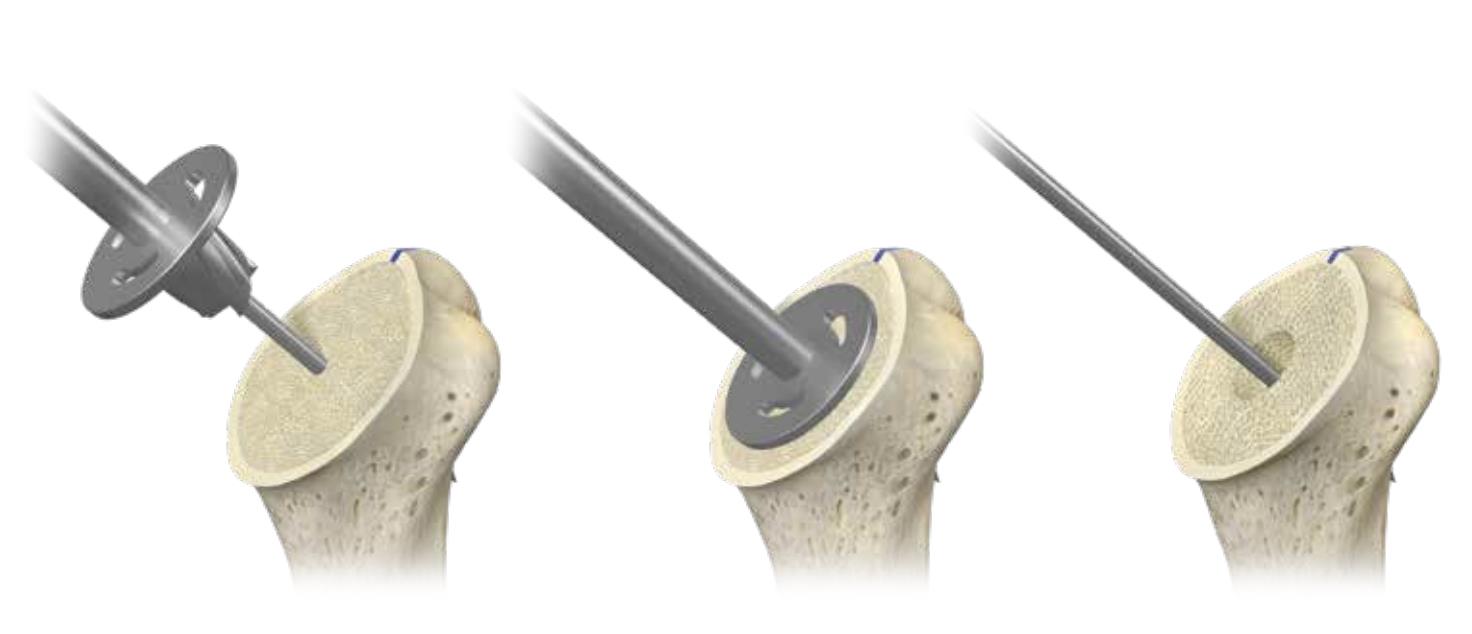

Summary The OsseoFit™ Stemless Shoulder System is indicated for anatomic total shoulder arthroplasty in patients where a bone-sparing, stemless solution is desired to maximize humeral fixation. It achieves this through OsseoTi® Porous Metal Technology and a site-specific fin design that creates a stable, biological press-fit while simplifying the surgical workflow with integrated suture holes. This system addresses a wide variety of patient anatomies using its versatile inlay and onlay size options. Indications Indications osteoarthritis indicated for anatomic total shoulder applications Contraindications local/systemic infection, sepsis, and osteomyelitis active local or systemic infection sepsis osteomyelitis inadequate humeral bone inadequate bone may lead to poor implant fixation large metaphyseal cysts may compromise stemless fixation irreparable cuff tear rotator cuff must be functionally reconstructable for anatomic total shoulder arthroplasty revision of any stemmed or stemless prothesis contraindicated for revision of any stemmed or stemless prosthesis Anatomy Osteology humeral head anatomic neck greater tuberosity lesser tuberosity bicipital groove metaphyseal cancellous bone Muscles deltoid forms the lateral border of the deltopectoral interval pectoralis major forms the medial border of the deltopectoral interval subscapularis released and repaired according to surgeon preference Ligaments glenohumeral capsule is released as needed to expose the humeral head and glenoid coracohumeral ligament contributes to rotator interval constraint superior, middle, and inferior glenohumeral ligaments contribute to anterior stability transverse humeral ligament overlies the bicipital groove Nerves axillary nerve courses inferior to the subscapularis and around the lateral humerus must be protected musculocutaneous nerve lies medial to the coracobrachialis and conjoint tendon suprascapular nerve is at risk with aggressive posterior-superior glenoid exposure Blood supply anterior and posterior humeral circumflex arteries arcuate artery is a terminal branch of the anterior humeral circumflex system suprascapular and circumflex scapular vessels Preoperative Planning X-rays A/P, scapular Y and axillary views evaluate bony anatomy, humeral head position, glenoid wear, deformity, and acquired bone loss use x-ray templates to estimate stemless humeral implant size assess whether an anatomic total shoulder reconstruction is appropriate CT assess bone quality and identify any humeral bone tissues use to assess bone quality and identify humeral bone issues that may affect implant selection evaluate metaphyseal bone stock, cysts, avascular necrosis, deformity, and cortical support Approach Extended deltopectoral anterior incision with an optional biceps tenodesis beginning immediately above the coracoid process and extending distally and laterally, following deltopectoral groove along the anterior border of the deltoid Technique Humeral head resection expose the humeral head and identify anatomic neck landmarks fixed-angle resection targets 135° inclination and 30° retroversion select left- or right-specific extramedullary resection guide align the guide post with the humeral shaft for fixed-angle resection align the 30° version rod with the forearm flexed at 90° place pins to define version and inclination and to stabilize the cutting surface resect the humeral head through the far side of the humeral head adjust the resection with the guide or calcar planer if needed assess bone quality with direct pressure perpendicular to the resected surface consider stemmed humeral fixation if cancellous bone is easily depressed or primary stability is questionable Humeral protection during glenoid preparation select the humeral resection cover that most closely fits the resected surface prepare the glenoid using the appropriate compatible glenoid technique remove the humeral resection cover before humeral sizing Humeral sizing place the humeral sizer onto the resection surface select the size intended to optimize cancellous bone fixation without violating the inner cortical rim orient the sizer so the bicipital groove bisects the superior and anterior fins insert the central Steinmann pin through the center of the sizer and through the lateral cortex avoid deep lateral cortical penetration to reduce risk to the axillary nerve place a lateral humeral retractor as needed to protect the axillary nerve confirm sizing after any additional planing Humeral bone preparation (boss reaming) ream until the boss reamer bottoms out on the resected surface ream over the central Steinmann pin with the boss reamer protect the lateral humerus and axillary nerve with a retractor remove the boss reamer while leaving the central Steinmann pin in place Humeral bone preparation (broaching) select the reference foot based on implant size select the broach that corresponds to the humeral sizer align the broach superior fin with the superior indicator line on the broach inserter slide the assembly over the central Steinmann pin until the broach contacts the resection surface remove the inserter-reference foot assembly and central Steinmann pin perform broach stability testing consider stemmed humeral fixation if the broach is unstable Humeral head trialing determine humeral head diameter and height using the humeral head sizing template or the resected humeral head seat the head trial assembly into the broach rotate the trial assembly with the hex driver to assess coverage of the resection surface confirm alignment with the anterior and posterior borders of the humeral resection increase offset if the head trial does not cover one side of the resection decrease offset if the head trial overhangs the resected bone reduce the joint and perform trial range of motion record the final offset letter or interval on the proximal humerus remove and disassemble the head trial assembly Implant insertion remove the broach with the slap hammer while maintaining an on-axis trajectory use the same reference foot size used for broach insertion select the implant size corresponding to the final broach and operative side slide the reference foot down until it uniformly contacts the resection surface confirm superior fin markings on reference foot, implant, and bone are aligned disengage the inserter-reference foot assembly with axial traction and slight rotational force as needed onlay implant center boss is slightly proud of the resection surface, with fin top surfaces flush inlay implant sits below the resection surface Humeral head implantation select the final humeral head implant matching the trial diameter and height use the offset letter or interval determined during trialing place the humeral head into the concave surface of the impactor base on a rigid sterile table impact the adapter into the humeral head with the disposable impactor using a mallet, strike the head impactor at least twice until the humeral head is flush with the resection visually confirm uniform seating consider implant subsidence and stemmed fixation if no pre-impaction gap is present Technical specifications Implant design anatomically shaped asymmetric anchor design designed to match natural asymmetric humeral anatomy designed to maximize cancellous bone fit and help avoid cortical impingement six-fin configuration with progressive tapered wedge design fins are designed for press-fit insertion each fin contains a fully porous window anterior suture holes are present for subscapularis repair Porous technology OsseoTi® Porous Metal Technology is used in the stemless implant porous architecture is designed to mimic human cancellous bone design incorporates a fully porous 3D printed OsseoTi® lattice within a titanium framework Technical specifications OsseoFit Onlay Anchor Implant Side Size Left 1, 2, 3, 4, 5 Right 1, 2, 3, 4, 5 OsseoFit Inlay Anchor Implant Side Size Left 1, 2, 3, 4, 5 Right 1, 2, 3, 4, 5 OsseoFit Humeral Head Adapter